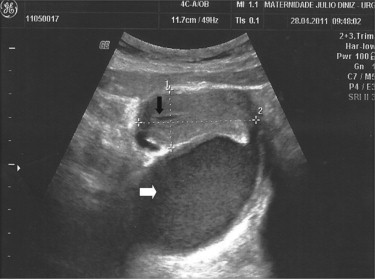

Ecograficamente, foi possível confirmar a ocorrência de distensão vaginal preenchida por conteúdo hipoecogénico (colpometra) e um hematometra laminar (fig. 3 ). Ambos os ovários eram normais. Analiticamente sem alterações de relevância; sedimento urinário e função renal normais.

Ecografia pélvica (seta branca: dilatação da vagina, hematocolpos; seta preta: ...

Figure 3.

Ecografia pélvica (seta branca: dilatação da vagina, hematocolpos; seta preta: hematometra).